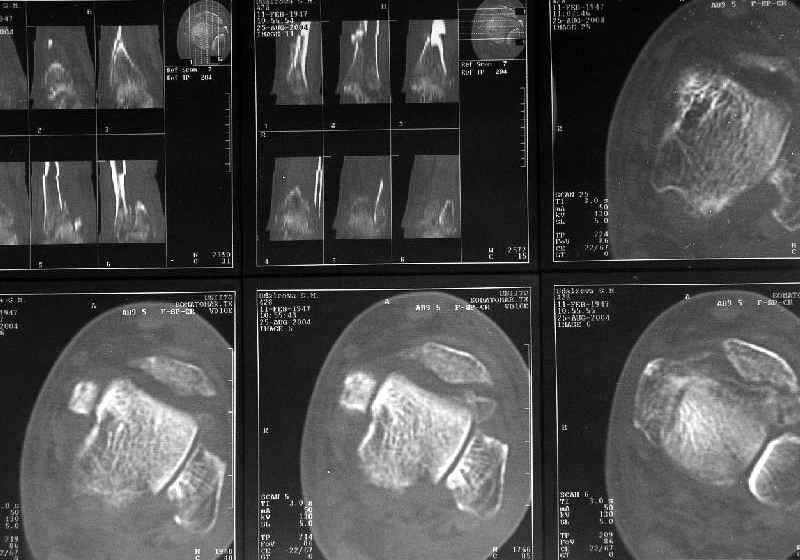

Однако именно по КТ как раз сложнее всего оценить состояние консолидации.

В этой связи БОЛЬШОЙ ВОПРОС:

Какова роль КТ при переломах диафиза длиннных костей:

- оценка положения отломков

- оценка сращения и пр.

В подавляющем большинстве случаев мне это исследование кажется неинформативным (я имею в виду исключительно диафизарные переломы).

В нашей, например, практике - никакая. То есть для диафизарных переломов - не пользуемся, т.к. необходимости не испытываем. Суставы, таз - другое дело.

Оно избыточно. Обычная рентгенография дает все, что надо, для оценки диафизарного перелома.

Здесь повреждение не диафизарное, смотрели состояние суставного конца кости и взаимоотношения таранной кости с этим шипом. Результаты КТ как раз повлияли на план, без нее пошли бы латеральным доступом, а после - передне-медиальным.

Для диагностики внутрисуставных и вколоченных переломов томография информативна и практична, а если есть возможность трехмерной реконструкции, то это и наглядно представляет характер перелома.